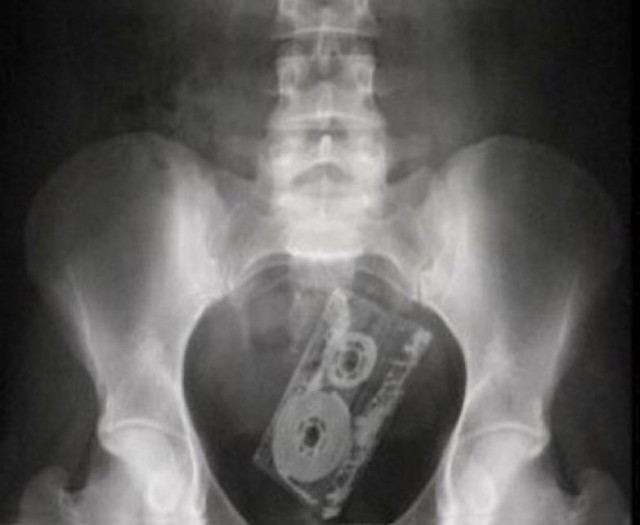

Аудио кассета

Когда не нравится чужая музыка